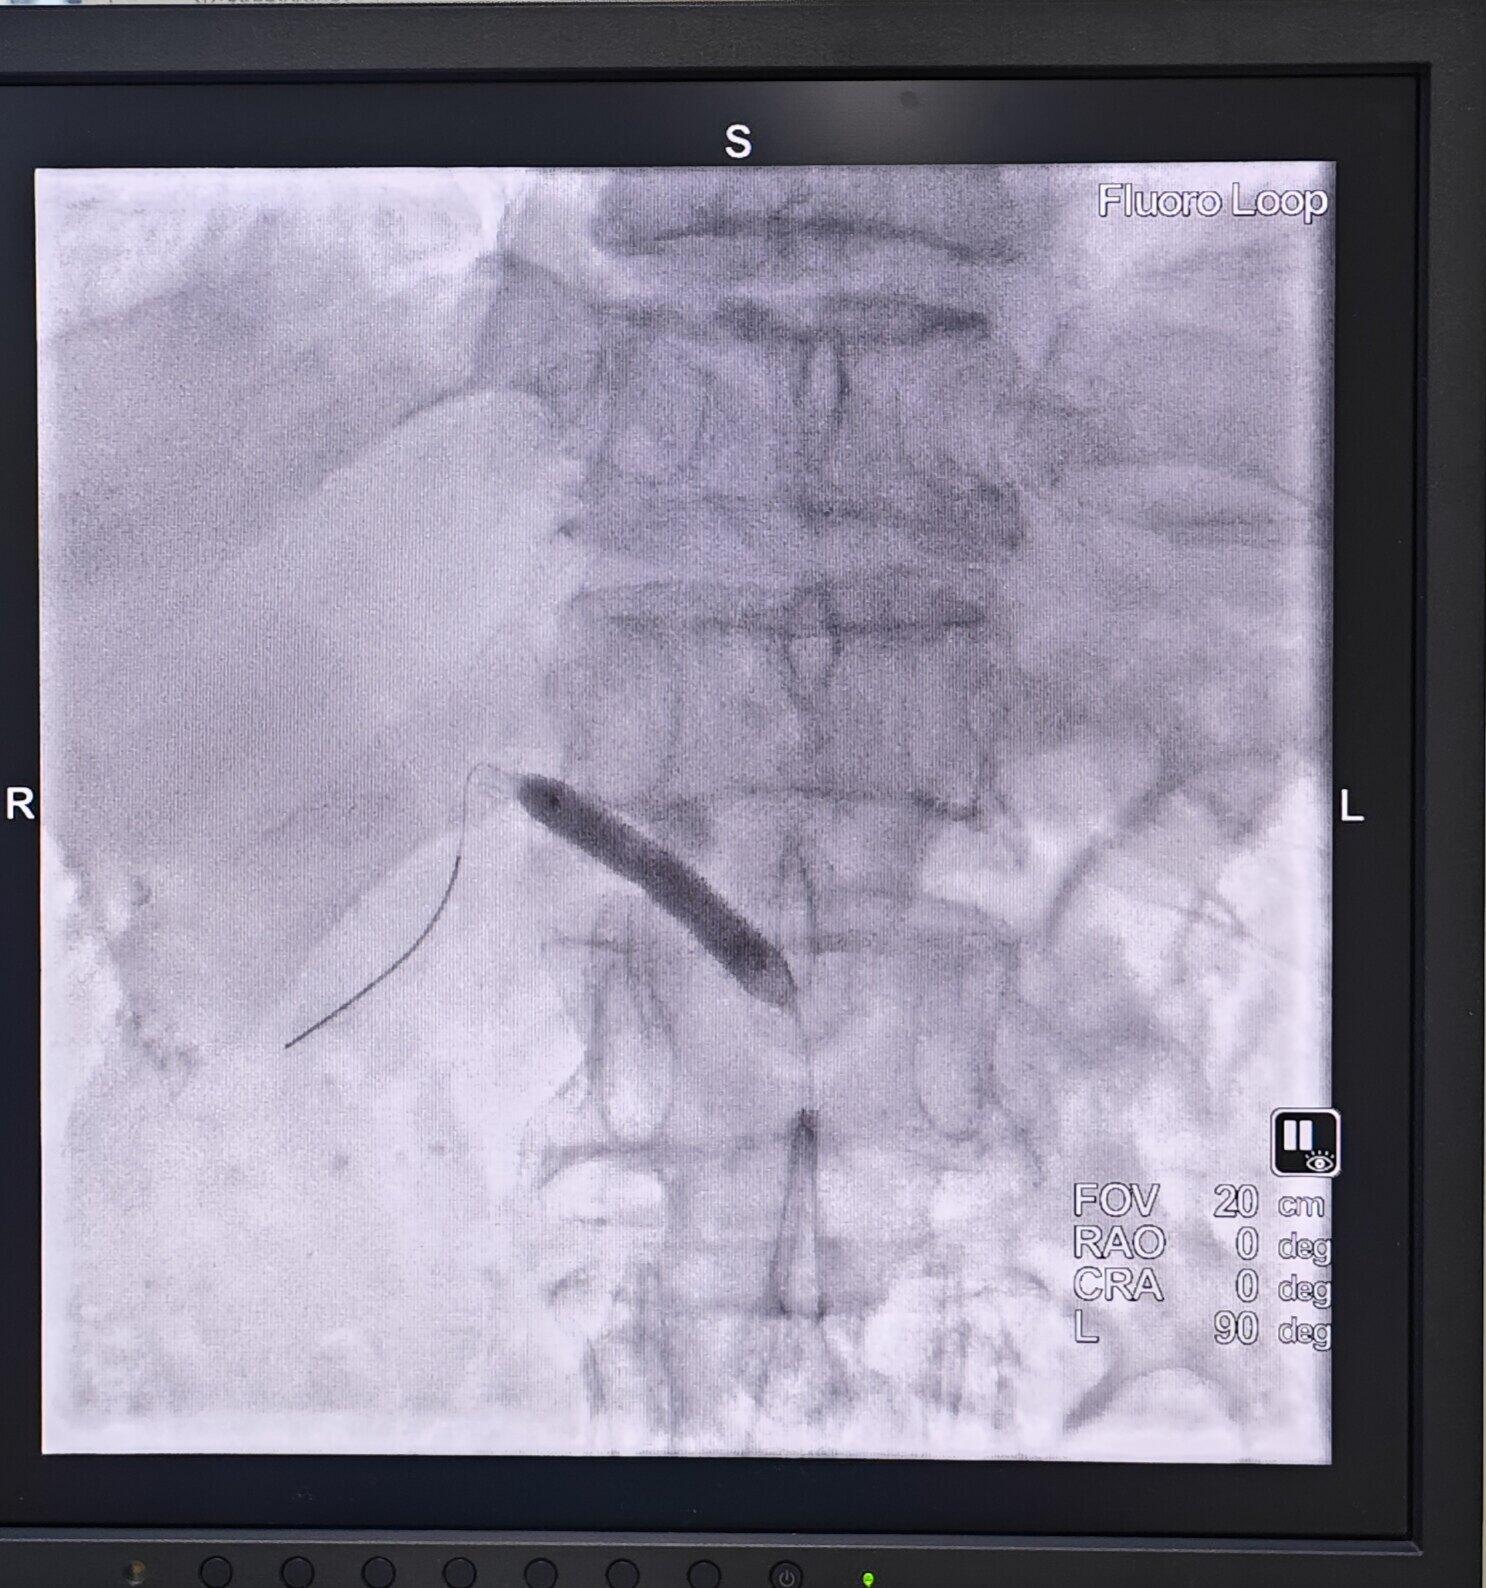

→_→肾动脉介入治疗过程:取仰卧位,常规消毒、铺无菌巾,局麻后穿刺股动脉并置入血管鞘。于患者的第1腰椎处放置猪尾导管行腹主动脉造影明确患者的肾动脉开口以及狭窄的情况。然后通过Cobra导管,进而选择肾动脉造影,从而使狭窄的程度、狭窄的部位、长度以及狭窄段两端正常RA的管腔直径得以明确。利用专用导丝和导管将选好的球囊和支架送到发生病变的位置,球囊扩张后准确释放支架。